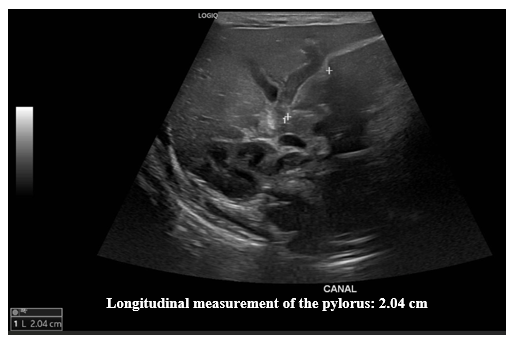

Ultrasound of the abdomen. The liver, gallbladder, bile ducts, pancreas, spleen, right and left kidneys, bladder, and retroperitoneum are normal. Additional examination focusing on the pylorus reveals a pyloric canal diameter of 20 mm, a muscle layer thickness of up to 5 mm, and an anteroposterior diameter of the pyloric canal of 16.4 mm.

Conclusion: Ultrasound findings suggestive of developing pyloric hypertrophy, to be correlated with current clinical presentation (Figures 1–3).

Figure 1 Pylorus ultrasound. Longitudinal measurement.

Ultrasound images of the pylorus showing a longitudinal measurement of 2.04 cm.

Ultrasound is the test of choice for the diagnosis of HPS. There are ultrasound parameters that allow the diagnosis of this entity to be made. Among these are the length of the pylorus, the muscle thickness and the diameter of the pylorus. However, there are variations in the measurements of these parameters. Piotto et al.,5 report studies where the measurements of these parameters vary, with pylorus length between 14-20 mm, muscle thickness between 2.5-4.8 mm, and pylorus diameter between 10-25 mm. In their study, Piotto et al.,5 found among 321 neonates without HPS an average length of 2.8 mm, standard deviation (SD) 0.6 mm; muscle thickness of 1.3 mm, SD 0.3 mm; and pylorus diameter of 8.2 mm, SD 1.1 mm. Among 286 neonates with HPS, the mean length was 16.3 mm, SD 2.3 mm, muscle thickness 2.9 mm, SD 0.5 mm, and pyloric diameter 38.4 mm, SD 18.5 mm. The ultrasound findings of our patient identified a diameter of the pyloric canal of 20 mm, a thickness of the muscle layer of up to 5 mm, and an anteroposterior diameter of the pyloric canal of 16.4 mm, all above normal values.